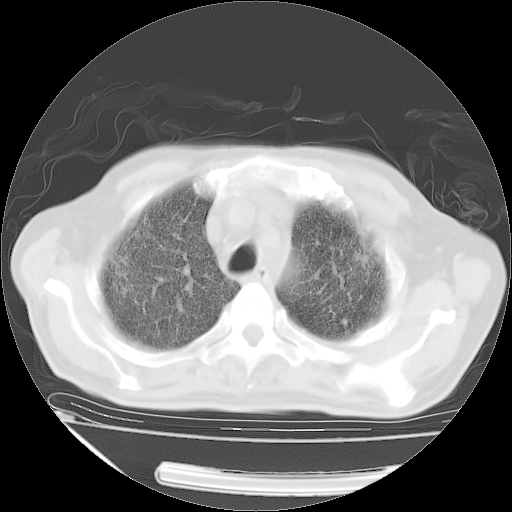

甲强龙80mg/日+抗结核治疗(异烟肼+利福霉素+乙胺丁醇)10天。复查肺部CT。

治疗10天肺部CT